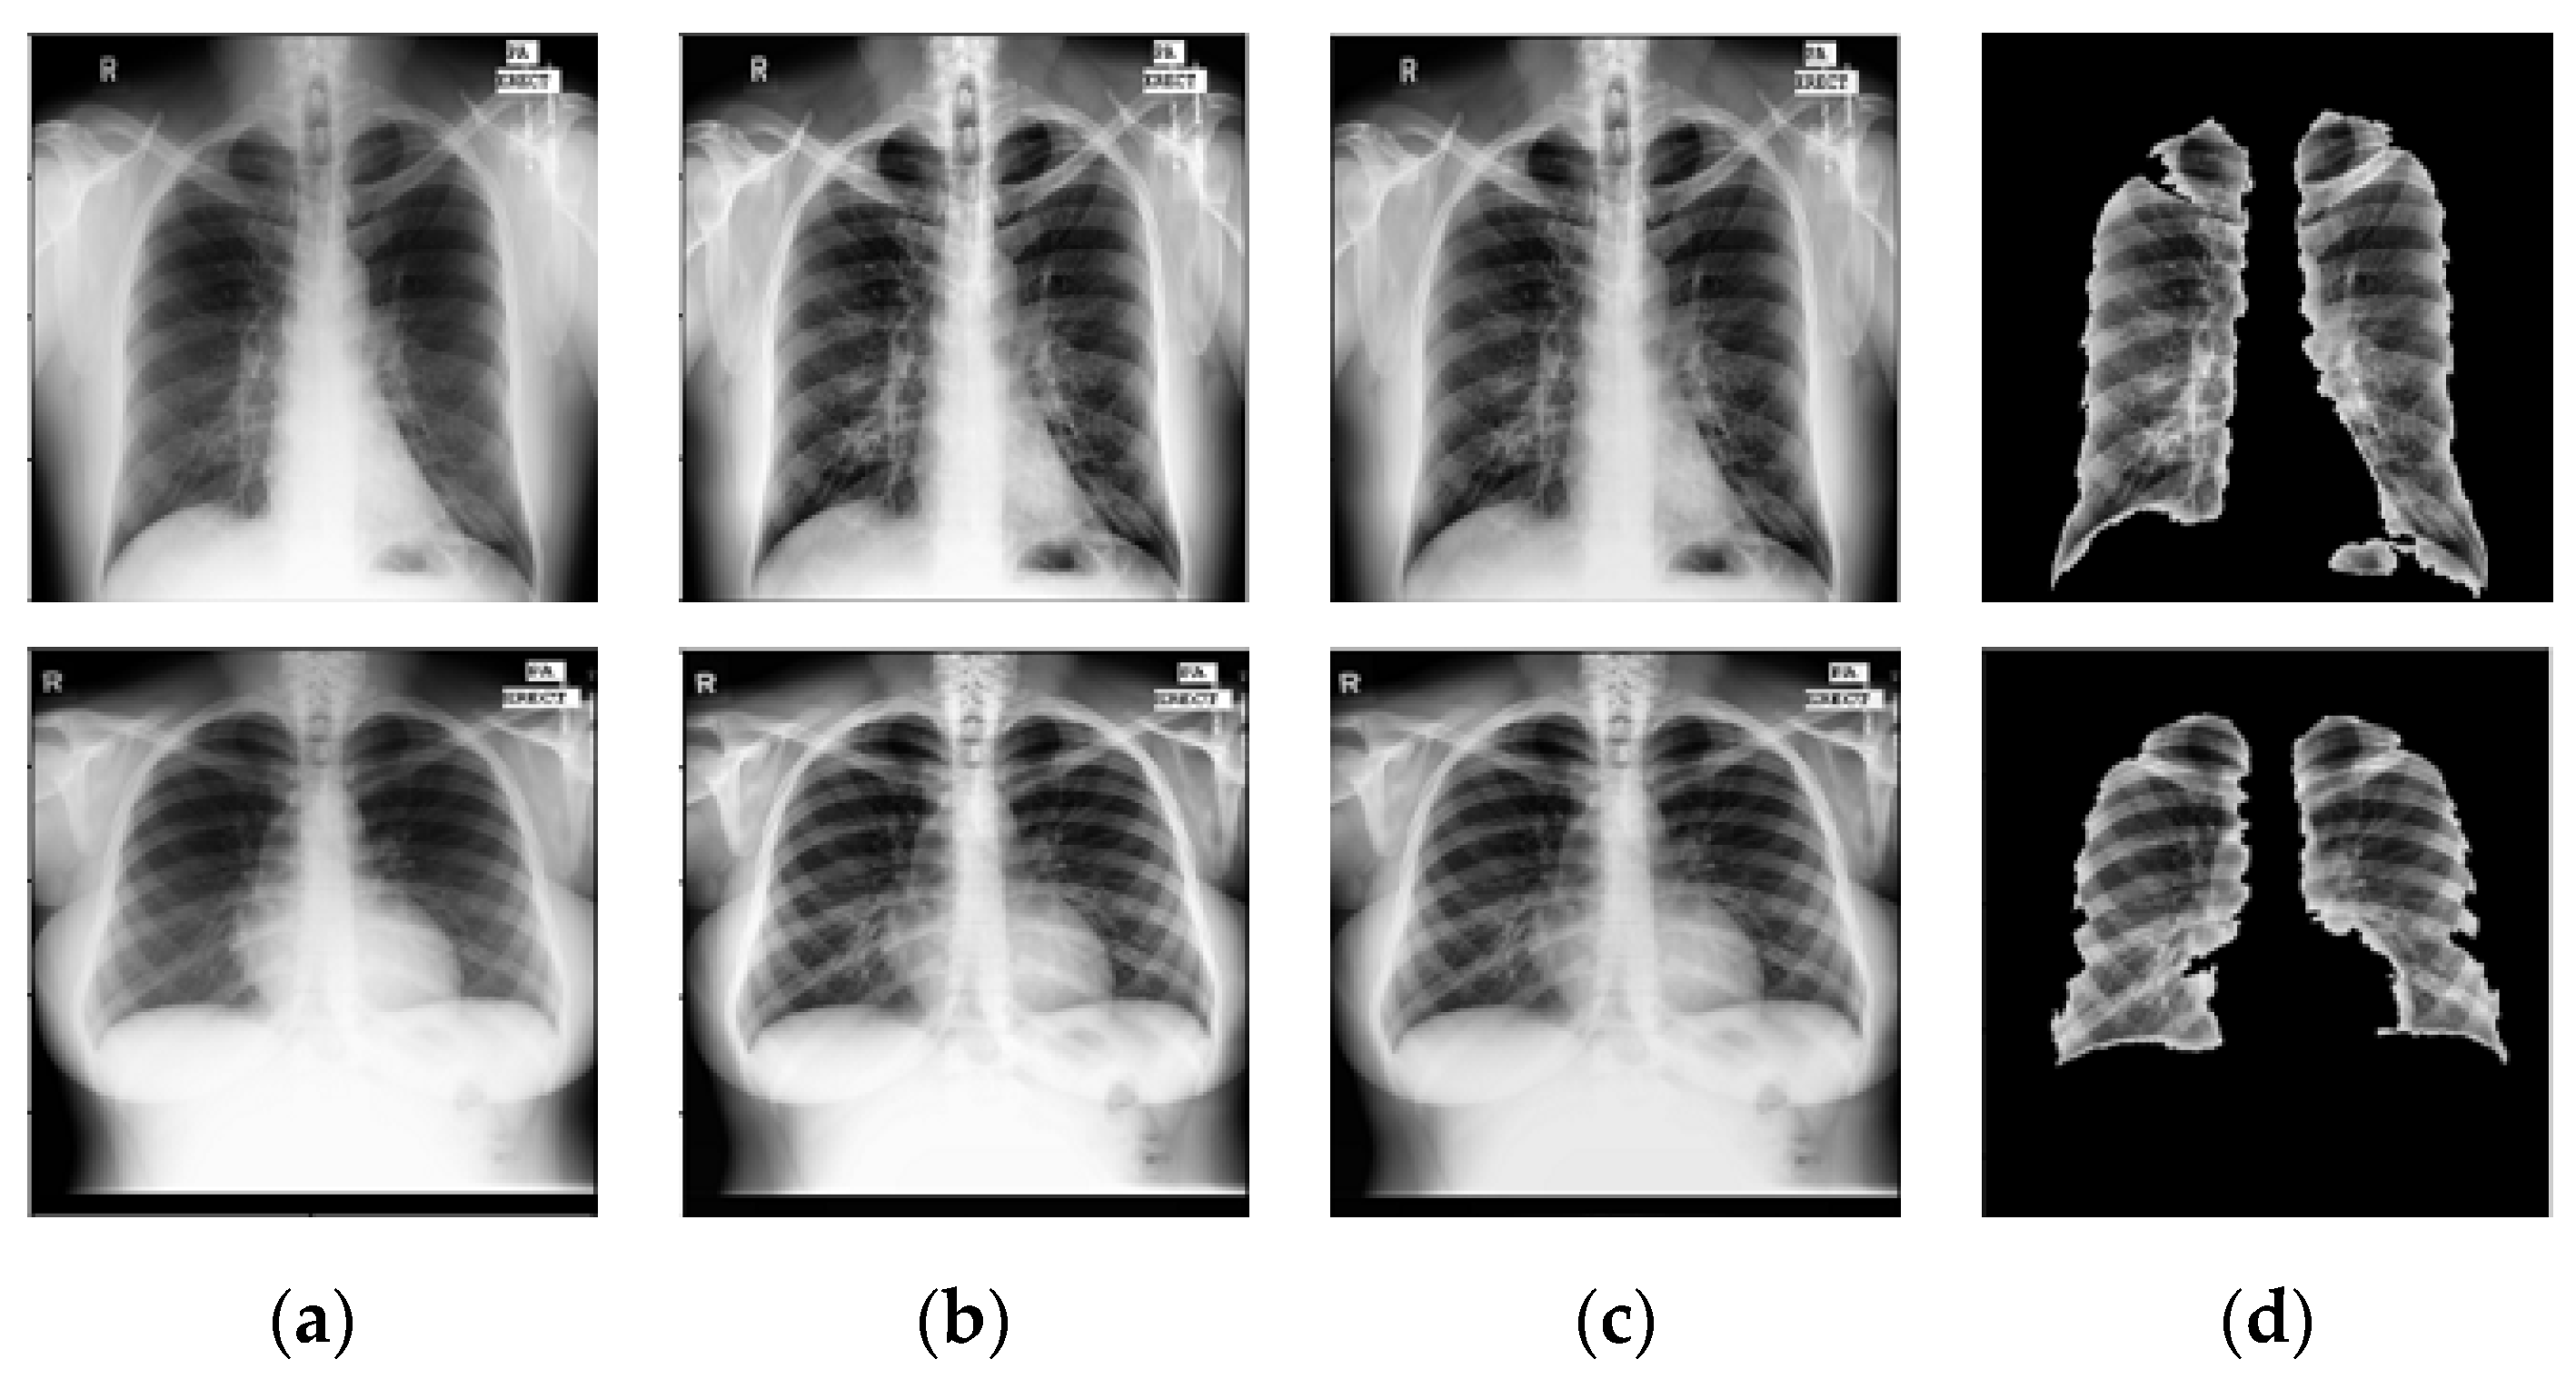

- NLM (National Library of Medicine) dataset [16,20,21]: This was made by two publicly accessible datasets including the Montgomery County CXR set (MC) and Shenzhen (CHN) dataset. The MC dataset was compiled in collaboration with Montgomery County, Maryland, the United States’ Department of Health and Human Services. The collection includes 138 frontal CXRs from Montgomery County’s tuberculosis screening program, where 80 CXRs were normal cases while 58 CXRs had TB manifestations. The X-rays were taken with a Eureka stationary X-ray machine (CR) and provided as 12-bit gray level images in portable network graphics (PNG) format. Moreover, the Digital Imaging and Communications in Medicine (DICOM) format is also available upon request. The X-rays were either 4020 × 4892 or 4892 × 4020 pixels in size. The Shenzhen dataset was collected in collaboration with Shenzhen No. 3 People’s Hospital, Guangdong Medical College, Shenzhen, China. The CXRs were from outpatient clinics and captured as part of the daily hospital routine within a 1-month period, mostly in September 2012, using a Philips DR Digital Diagnost system. The dataset contained 662 frontal CXRs, of which 326 belonged to normal cases while 336 had TB manifestations including pediatric X-rays (AP). The X-rays are provided in PNG format, and can vary in size, but is approximately 3 K × 3 K pixels.

- Belarus dataset [20]: The National Institute of Allergy and Infectious Diseases, Ministry of Health, Republic of Belarus, collected the Belarus Set for a drug resistance study. There are 306 CXRs in the dataset, representing 169 patients. The Kodak Point-of-Care 260 system was used to take chest radiographs with a resolution of 2248 × 2248 pixels. All images in this database had been infected with tuberculosis.

- RSNA dataset [20]: The RSNA pneumonia detection challenge dataset contains approximately 30,000 chest X-ray images, 10,000 of which were normal and the rest were abnormal as well as the lung opacity images. The DICOM format was used for all images. A total of 3094 normal images were taken from this database and the remaining 406 normal images were taken from the NLM database to create a normal database of 3500 chest X-ray images for this study.

6.1. Weiner Filtering

6.2. Prior TB Segmentation